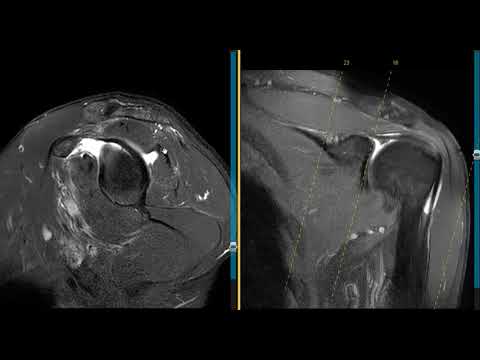

Массивный разрыв вращательной манжеты плеча у 58-летнего пациента